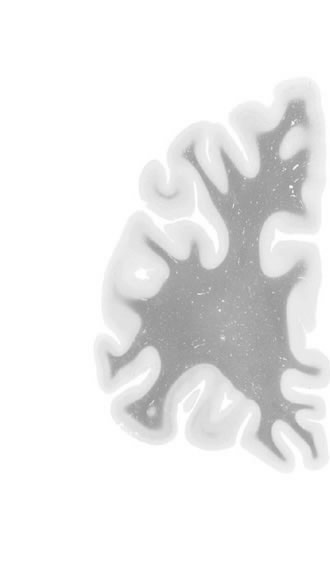

Hi-Resolution Sections · Cells (Nissl Staining) · Virtual Microscopy

Frontal sections (Nissl) from the Atlas Brain:

Macroscopy

Slice ID:

r1-0251

Plate NR:

04-05

Position:

-40,5 mm